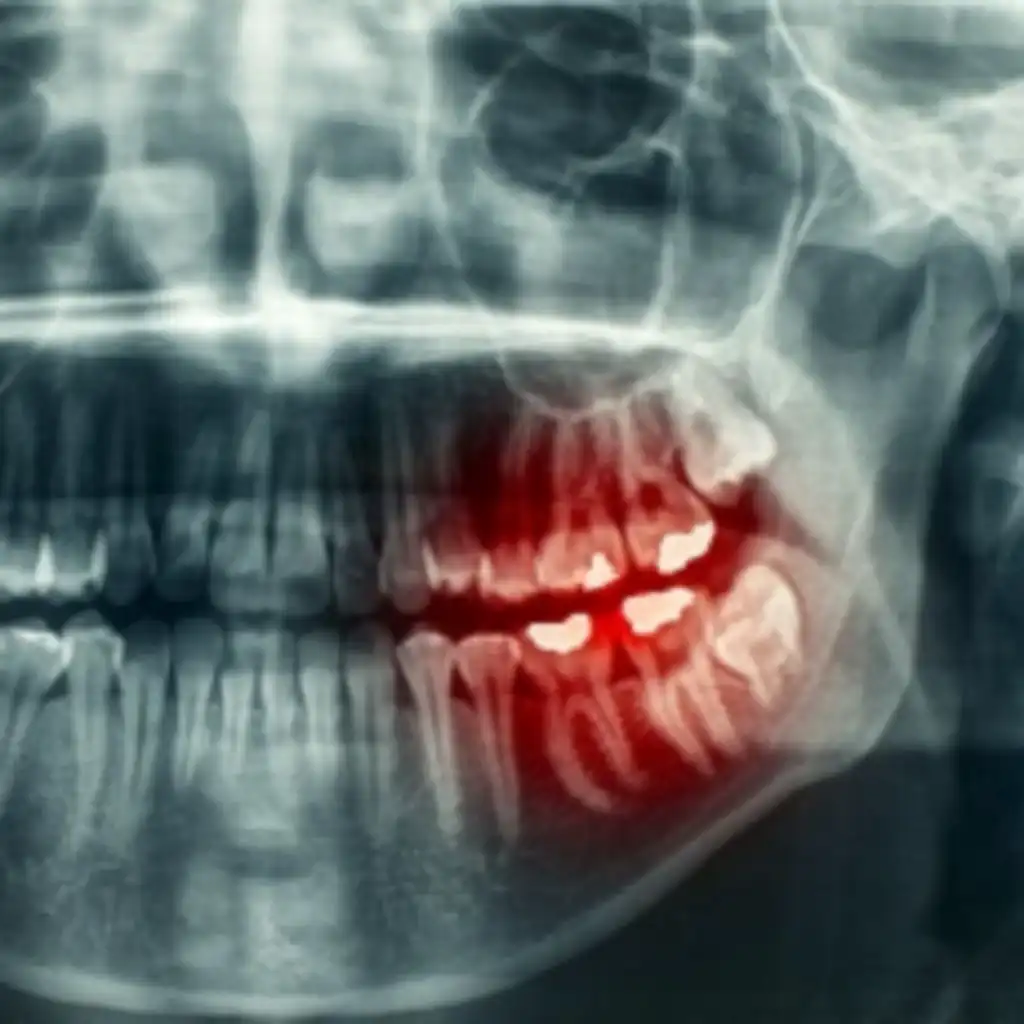

Podcast 844: Dental Infections

• Dental infections can be categorized into two main groups

• Infections of the teeth

• Periapical abscess

• Abscess that extends through the root of the tooth

• Can develop up elsewhere in tooth/gums/mouth

• Causes tooth sensitivity when tapped